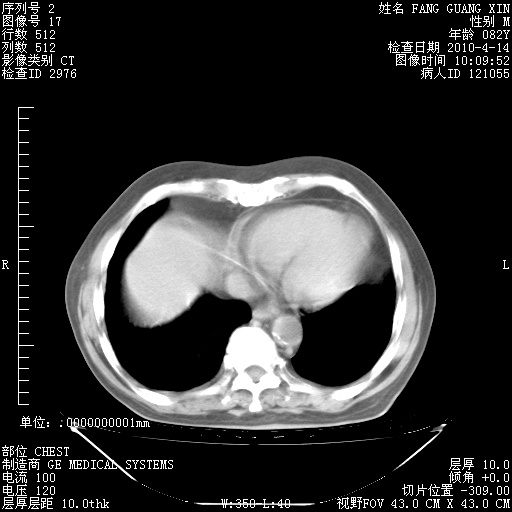

4月14日肺部CT